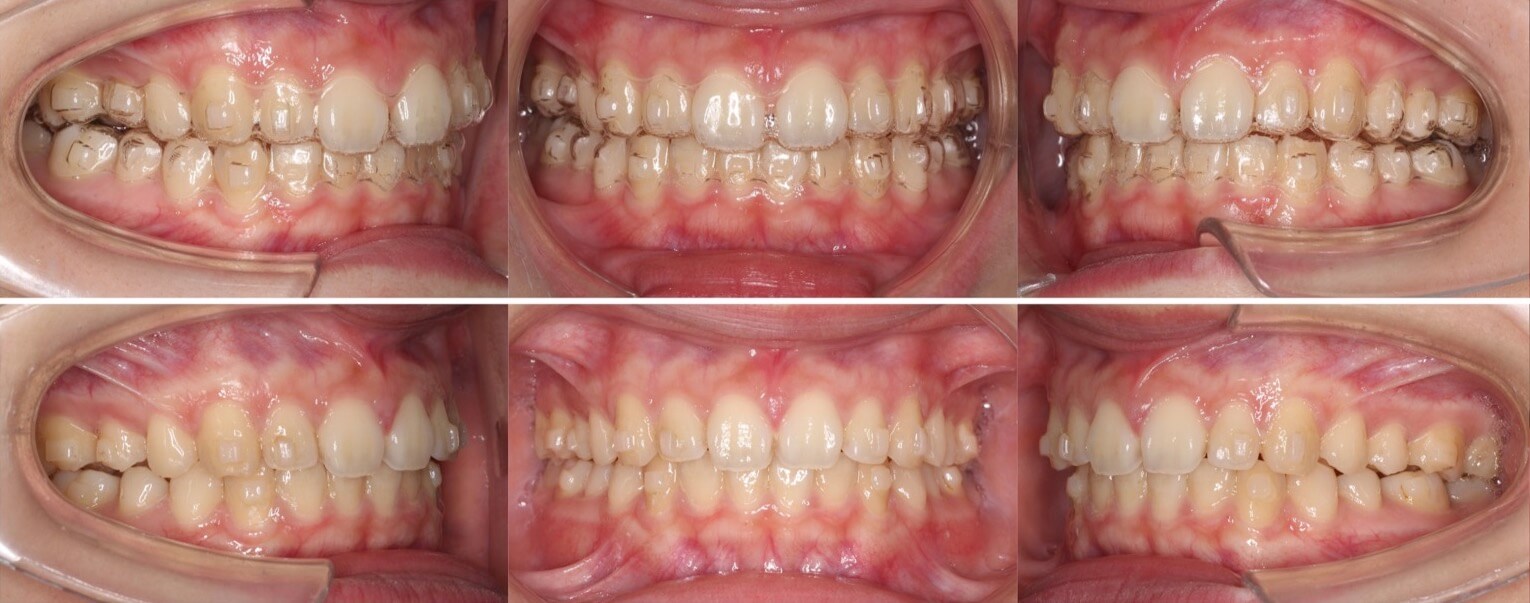

高校生男性・マウスピース型矯正

<症例概要> 難易度★★★☆☆

主訴:すきっ歯・前歯の突出

年齢・性別:高校生男性

症状:正中離開・過蓋咬合

治療方針:空隙閉鎖+左上歯列後方移動(左下歯列前方移動)

治療装置:マウスピース型矯正装置(アライナー装置)

固定装置:II級顎間ゴム

治療期間:1年2か月

アライナー枚数:35+11ステージ (7〜10日交換)

リテーナー:上フィックスタイプ+上下クリアタイプ

治療費用:990,000(税込)

隙間が上の前歯に数箇所あり正中線のずれもある少し難しいケースです。上下の前歯のギャップを、奥歯から歯を動かすことで正中線をそろえながら改善しました。

左上を順番に後方移動させることと、左下を順番に前方移動させることを組み合わせて、上顎前突と過蓋咬合だけでなく正中線の不一致も改善しています。